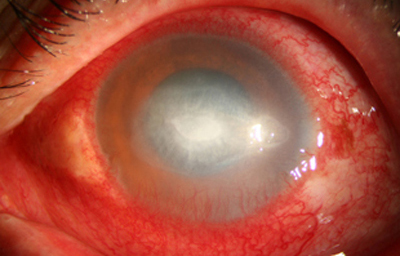

Superficie corneal irregular y grisácea, (Fig. 1, 2) con opácidades granulares en parche y formación de líneas epiteliales elevadas de aspecto granular (Fig. 3), que pueden arborizar dando imágenes de pseudodendritas. Opacidades superficiales satélites. (Figura 4) Inyección ciliar. Ulceración epitelial variante. (Figura 5).

Fig. 1 Síntomas de 15 días evolución

Fig. 2 Síntomas de 25 días evolución

Estas lesiones progresan con la aparición de infiltrados estromales anteriores difusos o focales, (Figura 6) edema circunscrito, y en ocasiones infiltrados en los nervios corneales (Figura 7), (perineuritis, usualmente entre las 1 a 4 semanas de evolución).

En su evolución se observará aumento del edema, agrandamiento y coalescencia de los infiltrados formando un anillo, (Figura 9, 10 y 11) que progresa hacia la formación de un absceso (Figura 12, 13 y 14), queratolisis superficial, adelgazamiento y perforación corneal (Figura 15 y 16).

Limbitis y escleritis anterior difusas.

La vascularización y el hipopion son poco frecuentes en los estadios tempranos de la queratitis. Con el tiempo, en los estados avanzados de invasión estromal, aparecen vasos estromales (Figura 17)